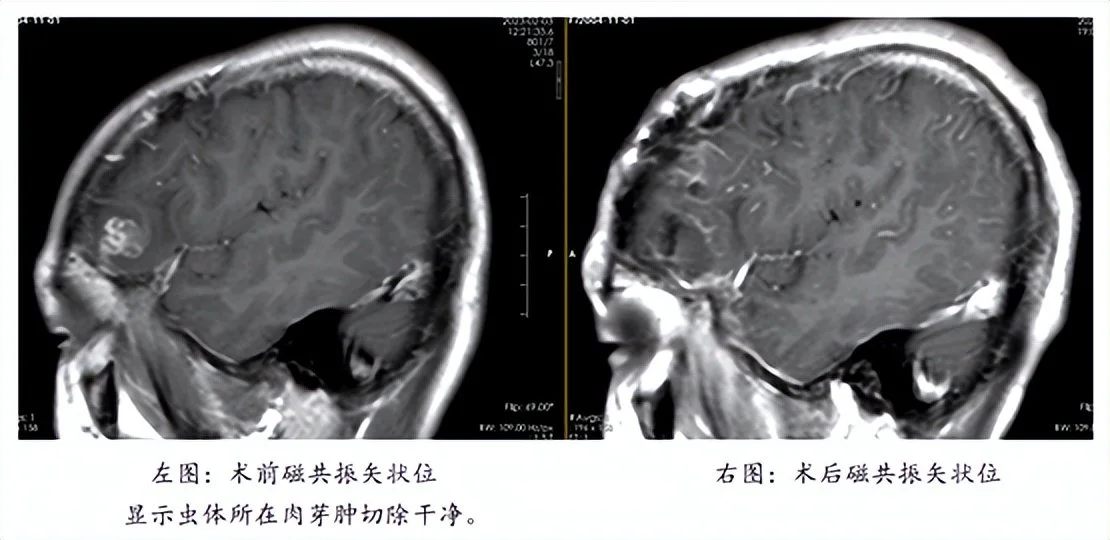

明确诊断后,需要进一步精准定位活虫在颅内的位置,因为颅内的多发脑软化灶是虫体在颅内的移动轨迹,通过间隔2周的薄层磁共振增强扫描,精准定位到寄生虫位置(左侧额叶前部)后,2月21日,陈俊喜带领团队为患者实施寄生虫抓取及肉芽肿切除术,最终从患者颅内顺利“活捉”一条长11厘米的裂头蚴,连同“虫窝”也一并切除了。